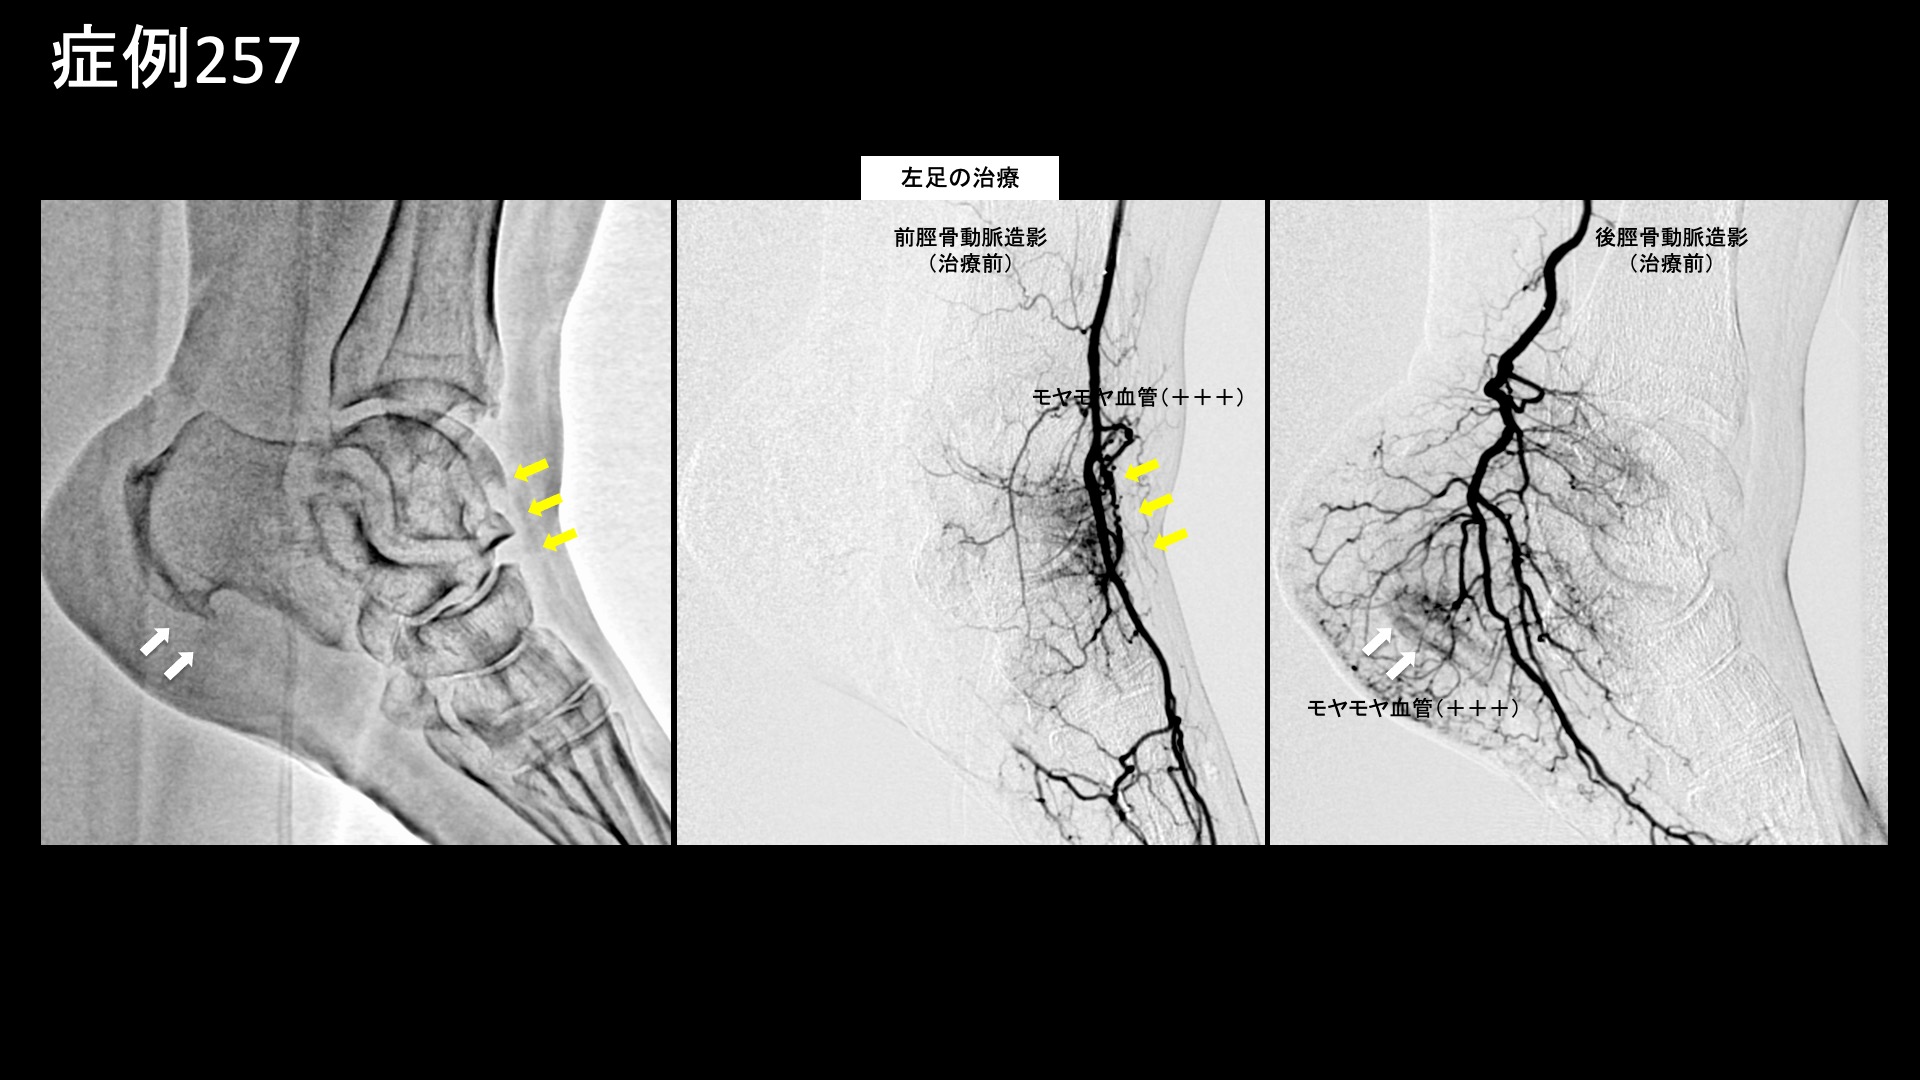

まず膝の治療から始めました。血管造影を行うと、全ての血管でモヤモヤ血管(病的新生血管)が造影剤の濃染像として描出されました。写真では、外側上膝動脈、下行膝動脈の造影所見を示しています。典型的な変形性膝関節症の所見です。治療後、モヤモヤ血管は画像上速やかに消失しました。続いて両足首および左踵の治療です。足関節は膝と比べると、ある程度重症度が増してこなければモヤモヤ血管が明確には描出されにくい部位ですが、本症例では主要3血管(前脛骨動脈、後脛骨動脈および腓骨動脈)の全てにおいてモヤモヤ血管が認められました。左足では、さらに踵骨棘近傍にも明瞭に描出されました。滞りなく治療を行い終了しました。